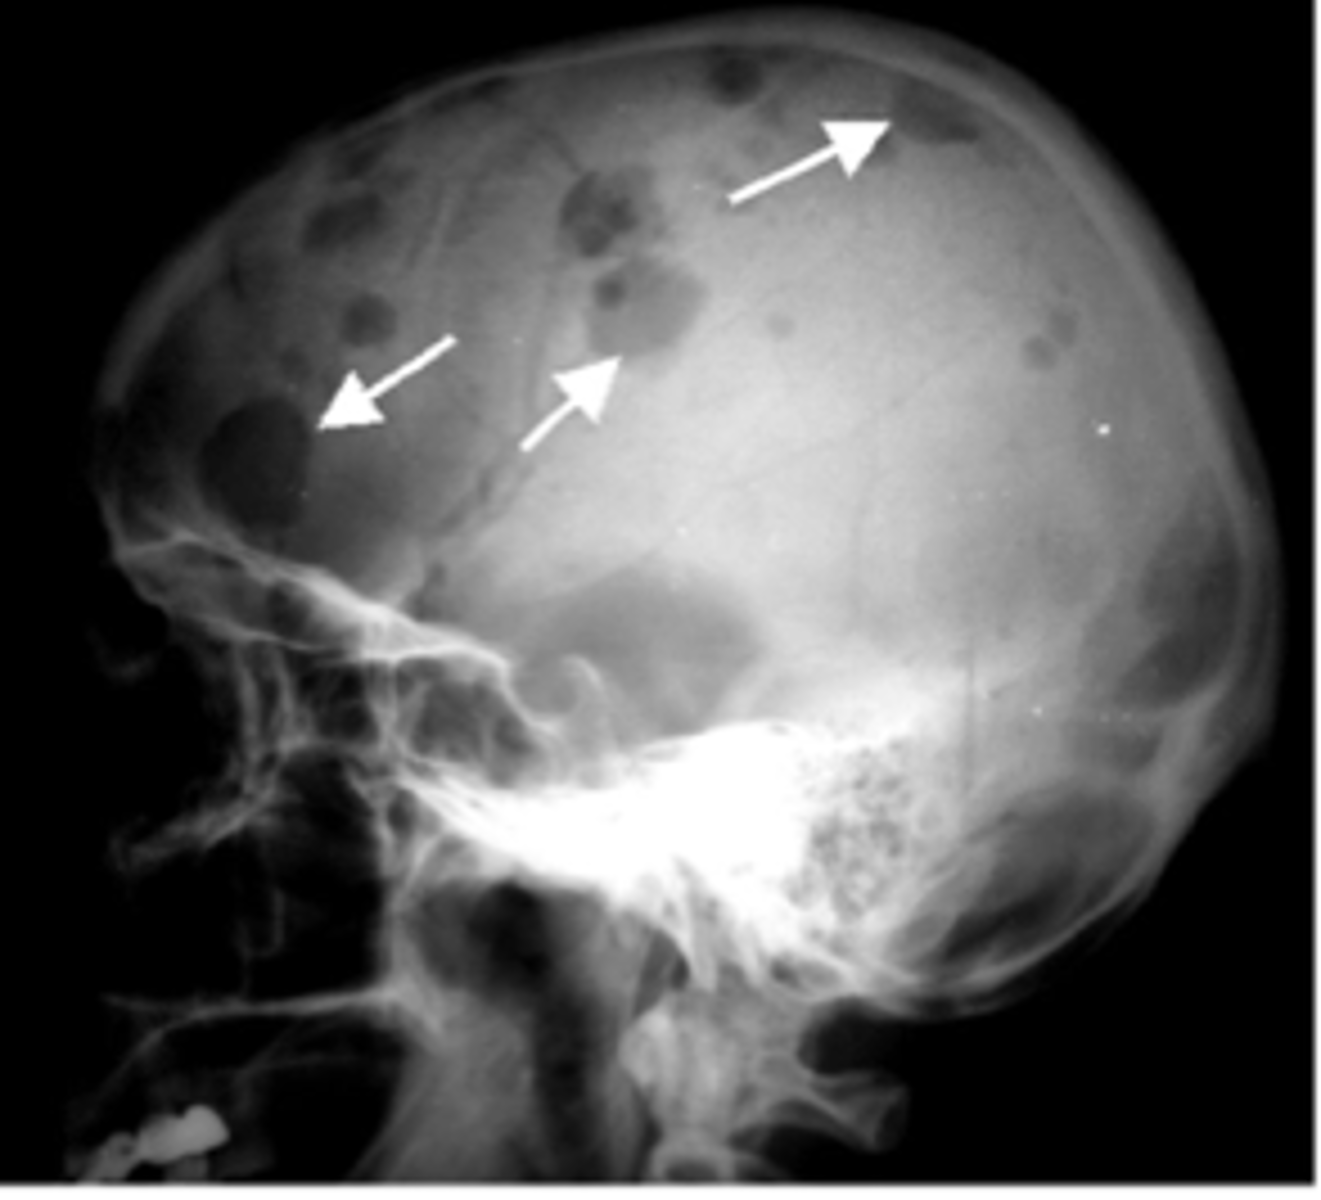

Defining characteristics of Multiple Myeloma

High antibody level, osteolytic lesions in bones